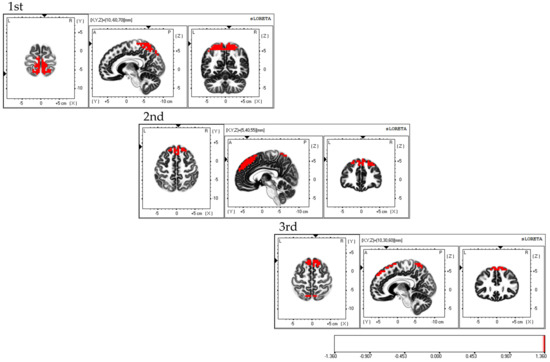

Considering the areas of brain activity during the FBT, the first and second sessions displayed parietal lobe predominance, mainly in the bilateral superior parietal lobes and activity in the bilateral supplementary motor areas, while the third session demonstrated a frontal lobe predominance, mainly in the dorsolateral prefrontal cortex and activity in the bilateral superior parietal lobes; the fourth session exhibited activity in the bilateral superior parietal lobes (Figure 5).

Figure 5.

Neural activity during FBT. The results of the EEG analysis using eLORETA during the FBT. During FBT, parietal-lobe-dominant activity is observed, mainly in the bilateral superior parietal lobes during the first, second, and third sessions. Bilateral supplementary motor cortex activity is also observed during the three sessions. The eLORETA scale depicts brain regions with activity values above two standard deviations of the neural activity value (µV/mm2) as red regions. FBT: forearm bisection test; eLORETA: exact low-resolution brain electromagnetic tomography.